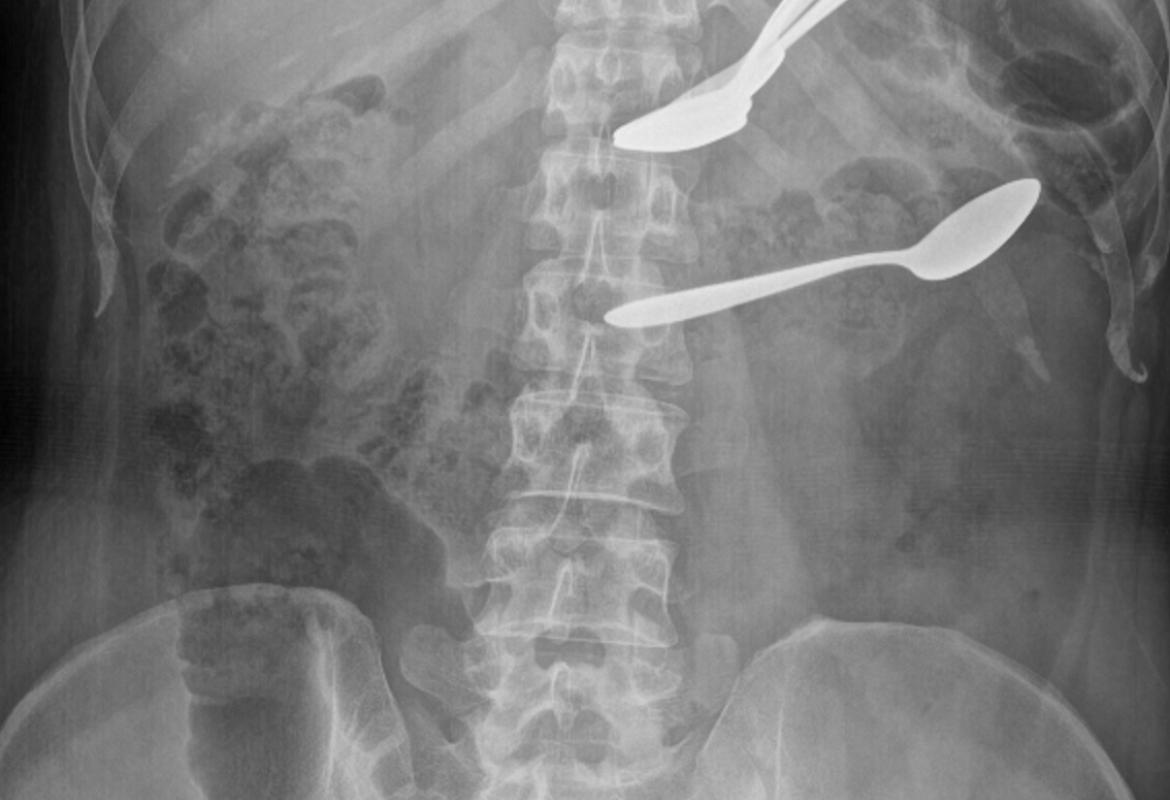

Foreign bodies in the stomach and transverse colon on abdominal X-ray

Successful Conservative Management of Multiple Spoons Ingestion in a Psychiatric Patient - An Unusual Case Report